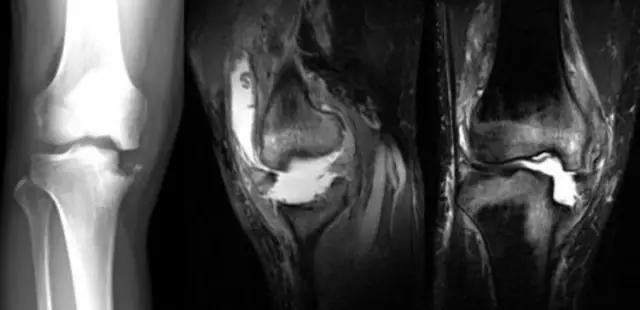

我们可能都不熟悉T1、T2,怎么办?当我们发现有问题后,利用照片上图像的对比,推测病变的可能也是一种诊断方法。病例:黄XX,女,39岁,左膝关节反复交锁1年。图1:肿物信号与骨信号一样图2:肿物信号与骨信号一样图3:肿物信号与骨信号不一样 肿物应该与骨相关,但不是骨性,推断:膝关节滑膜软骨瘤。手术后得到证实。